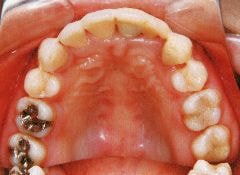

治療例1 (インプラント補綴+矯正)